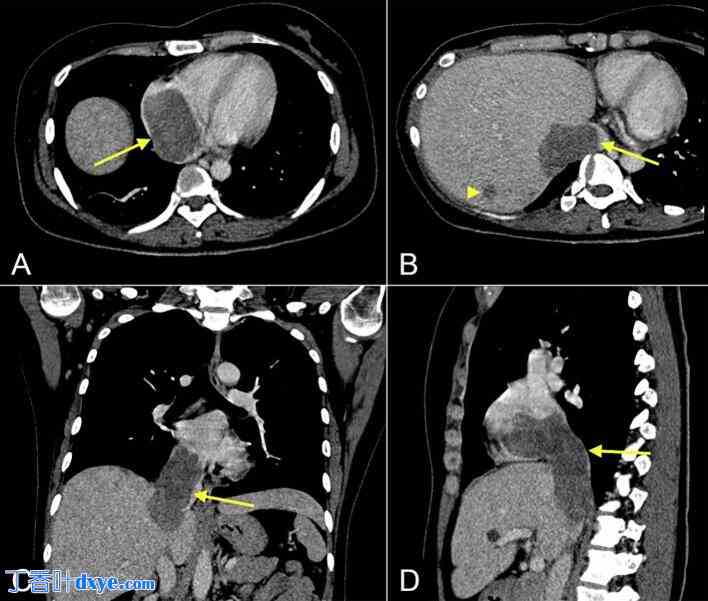

行胸腹部CT扫描,显示右心房、下腔静脉及右肝静脉内可见一巨大低密度、轻度强化肿块,可能侵犯肝脏VII-VIII段(图1)。子宫内亦可见多发肿块。双侧输卵管扩张并充满液体,右侧输尿管受压或粘连导致轻度肾积水。此外,肝VII段亦发现一结节,不能排除转移性病变。行盆腔MRI检查以筛查恶性肿瘤,结果显示多发性退行性子宫肌瘤(图2)。也考虑过子宫腺肌症合并平滑肌肉瘤的鉴别诊断,但可能性较小。脑部CT扫描未见脑部受累的证据。胸部CT未见肺部结节或肿块。

图2.

子宫磁共振成像显示一非典型平滑肌瘤(箭头),T1加权像(A)和T2加权像(B)呈不均匀高信号,DWI像(B)呈轻度高信号。